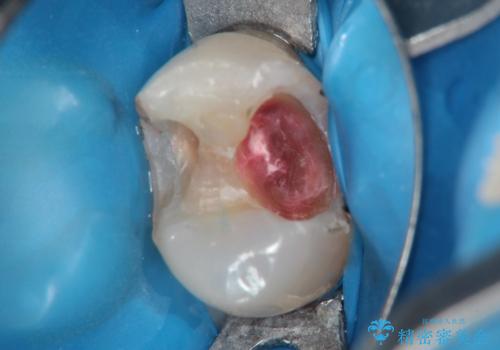

古い材料を除去すると中で虫歯が進行していたため、顕微鏡下で虫歯を除去した後セラミックインレー、PGAインレーにて修復治療を行いました。